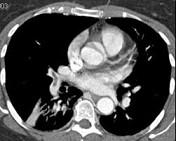

问题 男,56岁,食管癌术后,胸痛,呼吸困难,结合CT图像,最可能的诊断是 ( )

选项 A.食管癌肺转移 B.肺栓塞 C.支气管扩张 D.肺水肿 E.肺不张

答案 B